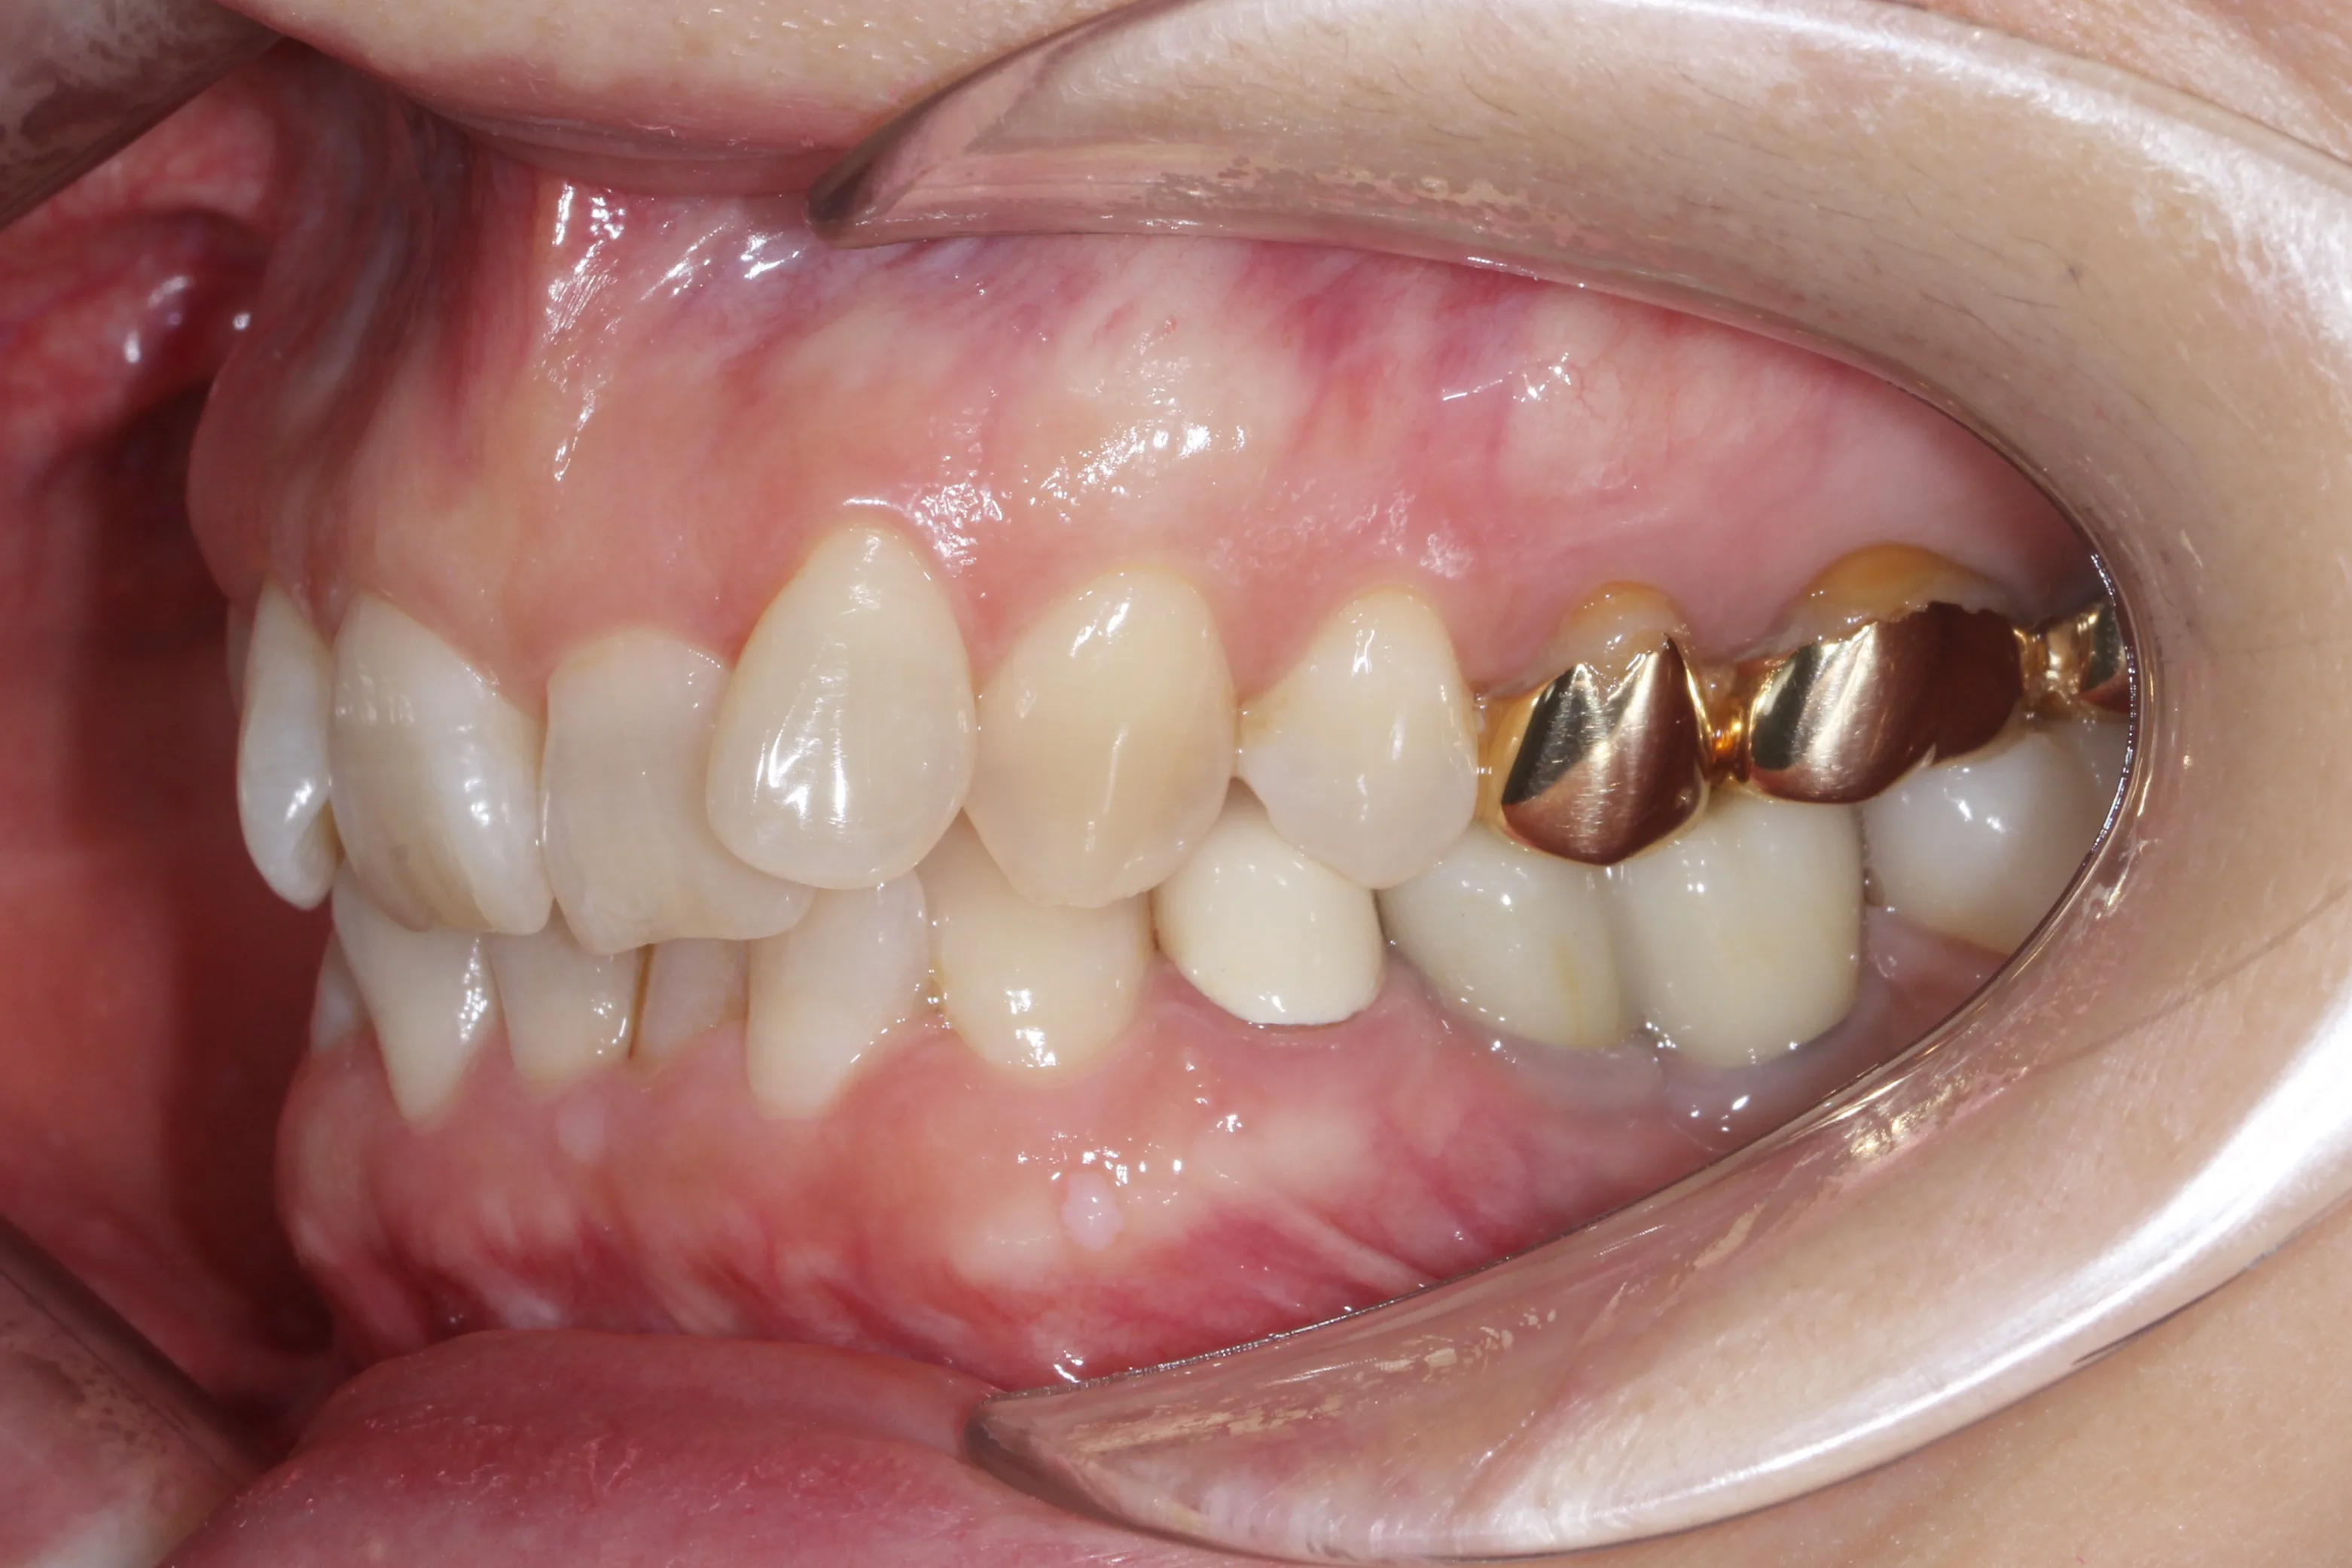

이 환자분은 이미 구강 안에 여러 개의 임플란트와 브릿지 보철물이 있는 상태였습니다. 앞니는 가지런하지 않고, 윗니가 아랫니를 깊게 덮는 과개교합(deepbite)도 있었습니다. 이런 경우 가장 중요한 것은 기존 임플란트와 보철물의 교합을 그대로 유지하면서, 나머지 치아만 가지런하게 배열하는 것입니다.

인비절라인의 디지털 치료 계획을 활용해서, 임플란트와 보철물이 있는 어금니는 움직이지 않도록 고정하고 앞니 위주로만 이동시켰습니다. 덕분에 발치 없이, 고무줄이나 미니스크류 같은 추가 장치 없이도 15개월 만에 치료를 마무리할 수 있었습니다.